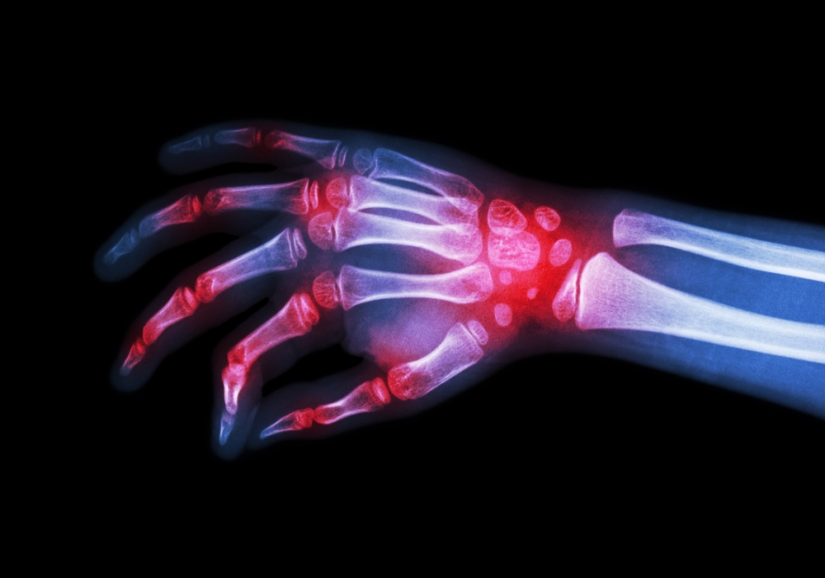

Artrite é inflamação de uma junta (articulação), porém pode ocorrer inflamação de várias juntas (poliartrite). O principal sintoma é a dor, que ocorre quando se faz algum movimento, ou mesmo quando em repouso. Pode haver inchação e vermelhidão. Quando há agente infeccioso, pode haver febre. Mas na artrite reumatóide é possível haver febre sem agente infeccioso.

A cartilagem articular é destruída pelo aparecimento de uma membrana anormal, o pannus. Numa segunda etapa o osso sofre progressiva degradação. A articulação perde toda mobilidade quando superfícies ósseas expostas se ligam (anquilose). As enzimas liberadas pelas células brancas, responsáveis pela fagocitose (digerem corpos estranhos), destroem os tecidos cartilaginoso e ósseo. O processo inflamatório enfraquece a cápsula articular e os ligamentos de reforço. Pode ocorrer comprometimento de músculos e tendões, que se atrofiam. Freqüentemente se formam nódulos, onde se acumulam fragmentos de tecidos mortos e células inflamatórias. Esses nódulos (nódulos reumatóides) são encontrados em áreas de maior pressão, como cotovelo e bacia. Podem aparecer na parte de trás dos dedos, presos aos tendões. Surgem até dentro do corpo, nos pulmões, pleura e coração.

A artrite reumatóide costuma surgir insidiosamente. Pode começar com sintomas vagos, persistentes, como cansaço, fraqueza, rigidez articular e dores fracas nos músculos e pequenas articulações das mãos, pés, punhos e tornozelos. No começo a doença pode atacar várias articulações ao mesmo tempo, especialmente as das mãos e pés. Mas há casos em que afeta uma ou algumas articulações, como a do joelho. Daí vai migrando simetricamente para outras juntas, deixando a primeira articulação doente cada vez pior. Em alguns pacientes essa “migração” não obedece a um padrão simétrico. Há casos em que a doença começa com artrite aguda: dores e edema em várias articulações, e febre. A evolução é difícil de prever. Alguns pacientes apresentam melhora espontânea, enquanto em outros a doença progride até assumir forma altamente consumptiva e incapacitante, confinando-os à cama.

As articulações apresentam-se inchadas, quentes e muito sensíveis. As mãos, frias e úmidas. Na doença de longa duração as manchas escuras sob a pele (equimoses) podem aparecer, principalmente em pacientes que usam corticóides. Podem surgir, com o tempo, nódulos reumatóides, mais freqüentes nos cotovelos. Geralmente não doem, mas às vezes se rompem e drenam cronicamente. Há casos, felizmente raros, em que aparecem nódulos no olho.